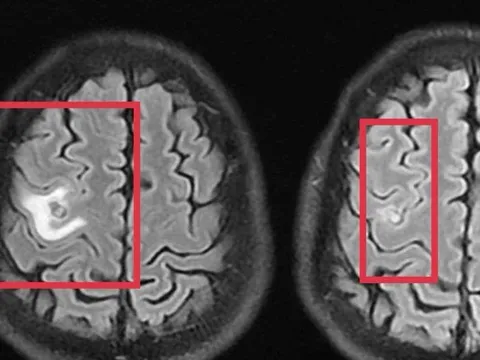

Đột quỵ khi đi vệ sinh lúc 2 giờ sáng 0

Người phụ nữ 75 tuổi méo miệng, yếu nửa người khi dậy đi vệ sinh lúc 2 giờ sáng, được gia đình đưa đến cơ sở y tế thăm khám và phát hiện nguy cơ đột quỵ.